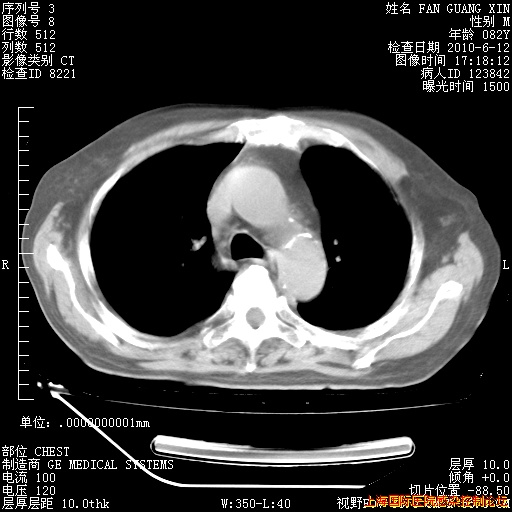

补发6月12日肺部CT肺窗

6月12日肺窗

6月12日纵膈窗